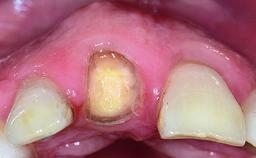

A 32-year-old female Caucasian patient with a compromised maxillary right central incisor was referred to us by a general dentist. Her chief complaints were discomfort and mobility of tooth 11 with unsatisfactory esthetics due to discoloration. The patient reported a previous trauma, some years earlier, as the origin of pathology on the afflicted tooth. Anamnesis was negative for any other dental or periodontal pathology in the remaining dentition. The patient did not take any medication and reported to be a light smoker (5–10 cigs/day). She had high esthetic expectations of her treatment. The extraoral examination revealed a high smile line with full exposure of her maxillary teeth and surrounding soft tissue in the area between the second premolars.